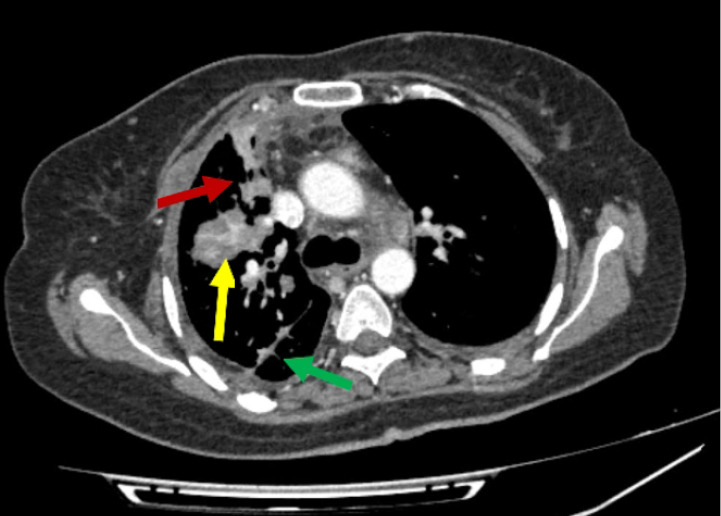

Case description: A 48 years old woman with no smoking history and no family history of cancer was diagnosed with EGFR mutation-positive advanced lung adenocarcinoma. Molecular analysis indicated a positive EGFR E19del mutation and a positive T790M mutation, and after two rounds of chemotherapy, the patient was treated with osimertinib for 2 years. However, the patient started to experience recurring chest discomfort, dyspnea, insomnia, and bone pain while being treated. A whole-body computed tomography (CT) scan at that time revealed metastasis of the tumor to the paraaortic lymph nodes and lumbar spine. A repeat analysis revealed that the T790M mutation had disappeared while other mutations remained unchanged, and she was switched to erlotinib as per the evidence for the use of erlotinib in osimertinib-resistant lung cancer. The patient developed cutaneous adverse reactions and, although her symptoms subsided initially for 6 months, she developed morning headaches and worsening insomnia. A repeat magnetic resonance imaging (MRI) revealed metastasis to the frontal and occipital lobes of her brain, indicating failure of erlotinib treatment.